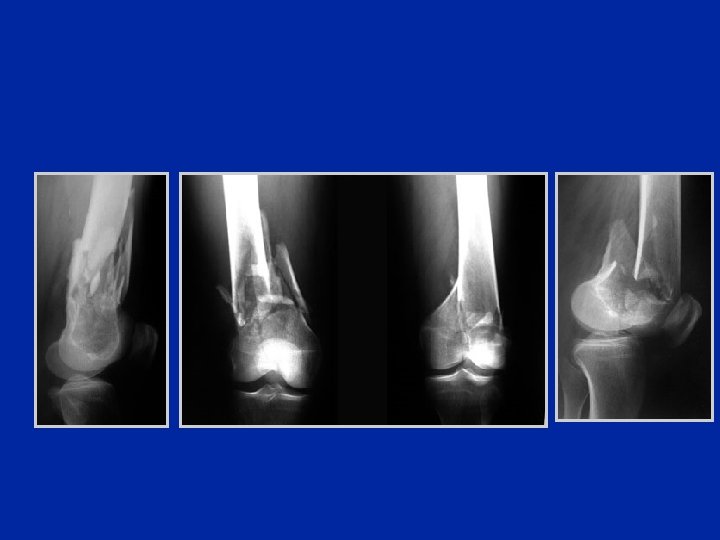

Fratture monocondiliche di Hoffa